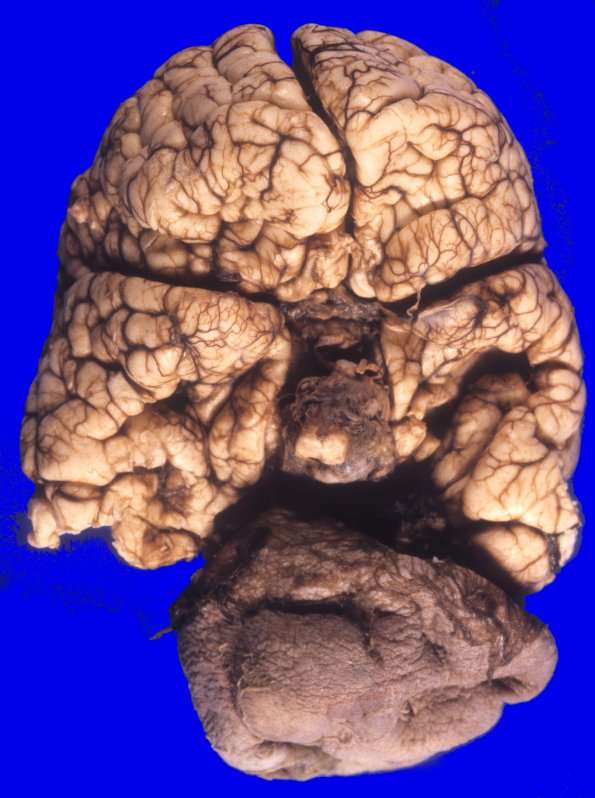

The gross appearance of the brain and encephalocele shows its extent compared to residual hemisphere in unfixed and fixed specimens. It appears to involve much of the occipital lobe, cerebellum and brainstem.